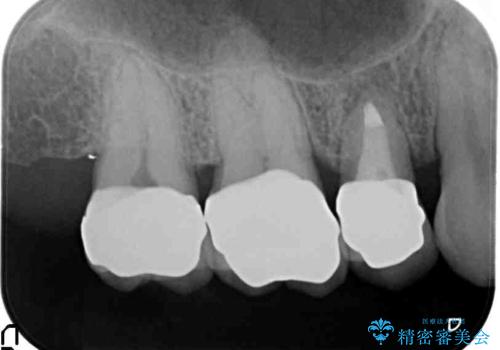

銀歯・虫歯を丁寧に除去したのち精密なセラミック治療を行うことで長期的な予後を目指します。

- 57万円(仮歯・ファイバーコア・ジルコニアクラウン×5)費用は治療当時の料金となります

銀歯をを外すだけでなく、セラミックを適合よく精密に製作することで長期的な予後を見込むことが可能になります。